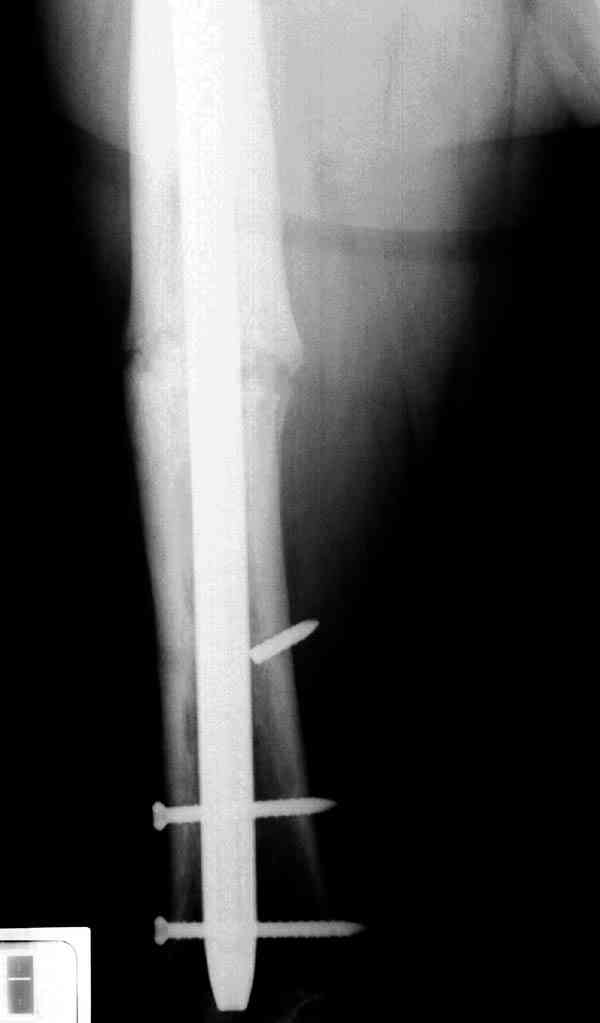

Сросшаяся малоберцовая как распорка привела к образованию ложного

сустава. В таких случаях удаляем сломанный штифт и проводим

стимуляцию ложного сустава рассверливанием. Рассверливание канала

создает стимуляцию на месте ложного сустава, и динамический вариант

блокировки штифта с большим диаметром создаст стабильность. Ранняя

нагрузка после остеотомии малоберцовой приведет к сращению ложного

сустава.

Приспособление для удаления сломанных штифтов и наличие ЭОП облегчит

задачу. При отсутствии крючка тогда можно применить обычный длинный

ball pointed guide wire от интрамедулярного набора. Проволока,

пропущенная за пределы гвоздя и зажатая другая вытащат сломанный

конец штифта без проблем.